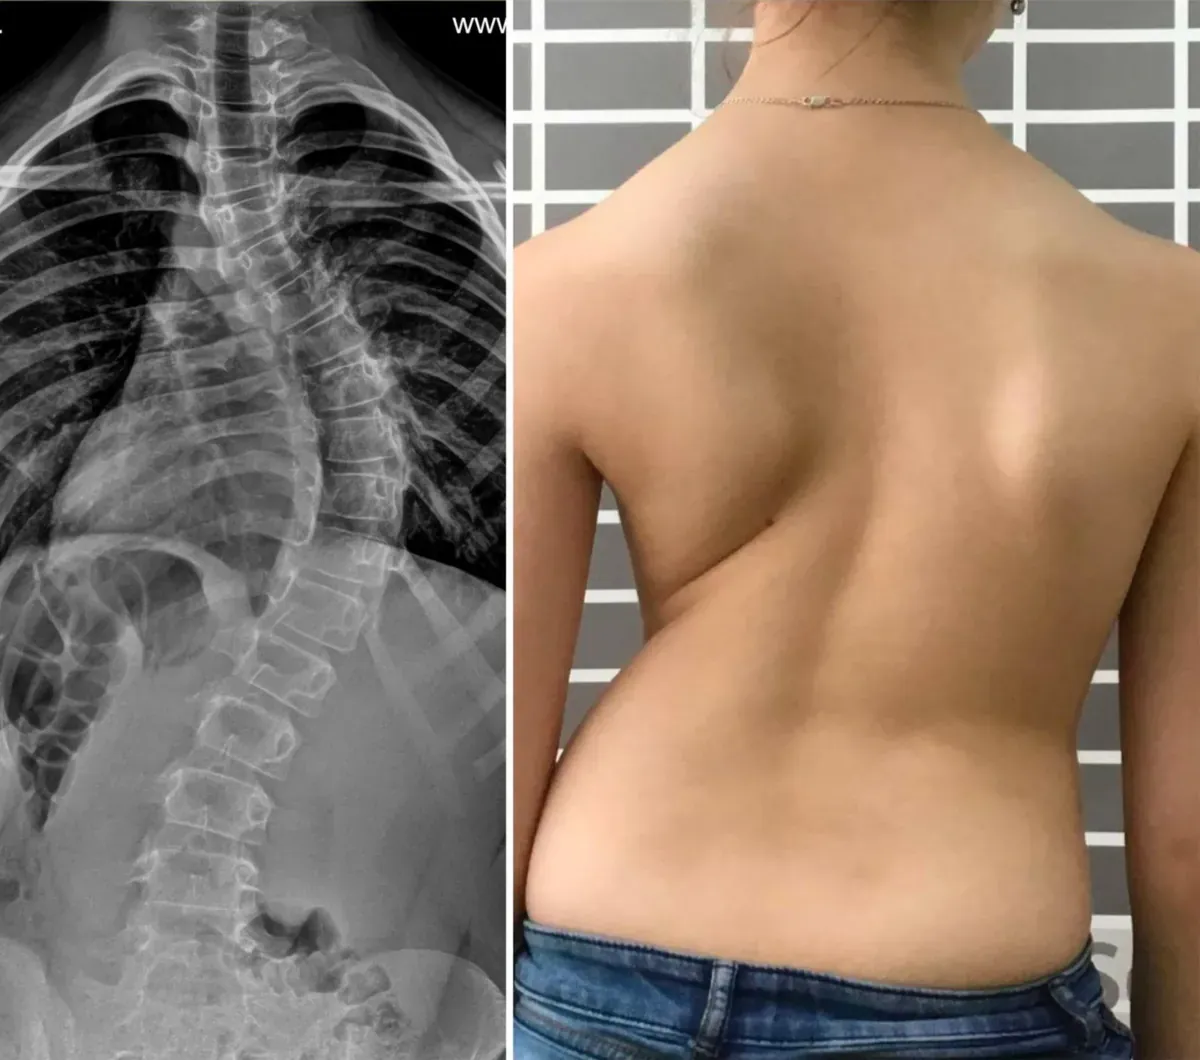

Dieses Mittel hat mich vor Verkrümmung und Rückenschmerzen bewahrt! Sitzarbeit und Osteochondrose sind unerträglich, die Ärzte waren ratlos – aber Veluflex hat wirklich geholfen, ohne Übertreibung. Verkrümmung und Wirbelsäulendeformation sind ernst! Besser früh gegensteuern. Hier mein Ergebnis:

Ich bin 71, Gelenk- und Rückenprobleme begannen vor 5 Jahren. Zuerst nur Schmerzen in Lende und Nacken. Ich dachte, nichts Ernstes. Dann fing es an, die Nerven zu quetschen! Schmerzattacken bis zu Tränen, man wollte nicht mehr... Vor Veluflex habe ich Dutzende Mittel ausprobiert – nichts half dauerhaft. Mit diesem Mittel eine enorme Erleichterung! Nach 1,5 Monaten der Rücken fast wieder gerade, mein Arzt sah die Bilder und war geschockt, fragte, womit ich mich behandelt habe.